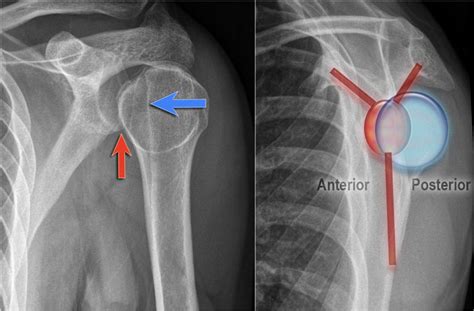

Anterior Vs. Posterior Shoulder Dislocation XR Y-View Scapular X-ray

dislocation shoulder posterior scapular ray anterior vs radiology xr imaging student anatomy